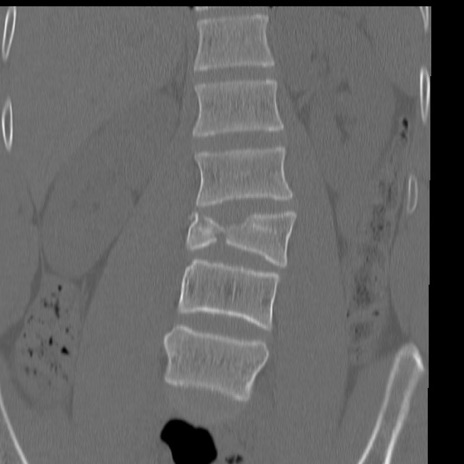

症例3 腰椎CT(冠状断像)

腰椎CT

矢状断像